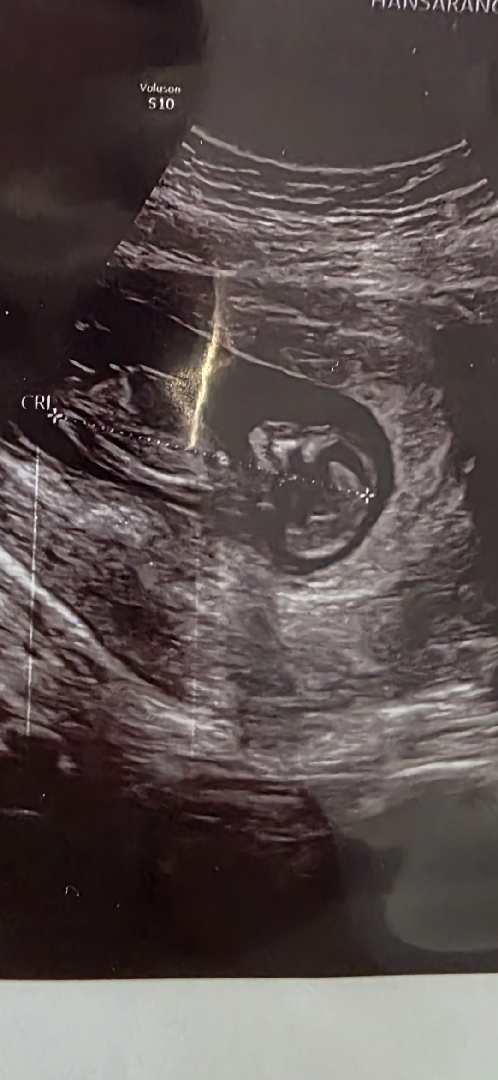

딸 아들 각도법 봐주세요오

내일이면 14주에요 >_< 이번달에 병원 가면 딸일지 아들일지 나올 거 같은데 너모너모 궁금해요오 각도법으로 아무리 봐도 모르겟어요 ㅋㅋㅋ 알려주실 부운